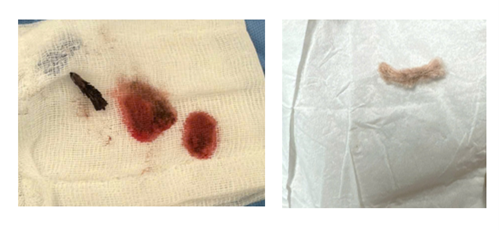

Hình ảnh chụp Xquang và đoạn kẽm nhung sau khi được bác sĩ phẫu thuật lấy ra ngoài

Sau đó, bệnh nhi được chỉ định phẫu thuật mở ngực khẩn cấp. Ê-kíp ngoại lồng ngực đã tiến hành mở phế quản gốc trái và lấy ra dị vật là một đoạn kẽm nhung dài khoảng 2 cm, dính máu cũ. Sau khi lấy dị vật, đường thở được làm sạch và khâu phục hồi.